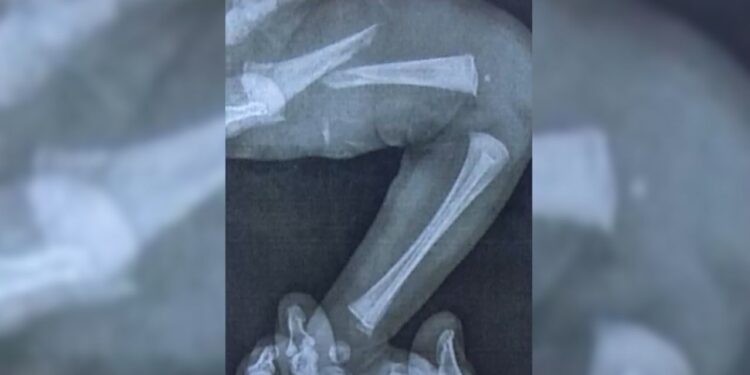

Em casa, a situação piorou. A bebê continuava chorando sem parar e desenvolveu inchaço e hematomas na perna esquerda. Depois de buscar atendimento em três unidades de saúde, um exame de raio-x finalmente revelou a gravidade: o fêmur da recém-nascida estava fraturado.